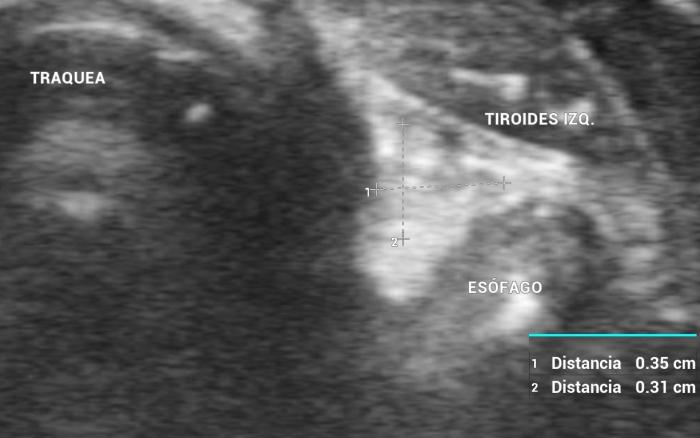

La localización anatómica superficial de la glándula, junto con su estructura relativamente uniforme, facilita su identificación mediante ultrasonografía de alta resolución. Entre los reparos anatómicos más importantes para su localización se encuentran las arterias carótidas comunes (laterales), la tráquea (medial) y los músculos esternotiroideos (ventrales), mientras que el esófago puede constituir una referencia dorsal del lóbulo izquierdo15 (Figuras 3 y 4).

En cuanto a los parámetros ecográficos de referencia, estudios realizados en perros han determinado que los lóbulos tiroideos sanos presentan una longitud entre 13-23 mm, ancho de 3-8 mm y alto de 2-5 mm, con variaciones según raza y tamaño corporal6. En gatos, las dimensiones normales son más pequeñas y oscilan entre 10-17 mm de largo, y 2-4 mm de ancho y alto, dependiendo de la edad y el estado funcional10 (ver además la Tabla 1).